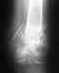

Прошу уважаемые форумчане помочь с проблемой. У друга перелом латерального мыщелка большеберцовой кости.

Травматологи ничего не говорят о тактике его лечения, а после беседы с врачом я так понял, что ее вовсе и нет. Сам я по специальности уролог и ничего не смыслю в вариантах лечения данной патологии но друг просит помочь. Снимок прилагаю

Наадо сделать КТ. И оперировать - надо восстанавливать форму суставной поверхности, т.е. поднять просевший мыщелок. Дефект заместить ауто- или алломатериалом. Фиксировать пластиной или аппаратом. Если в той больнице, где пациент сейчас, такие операции на потоке не делаются, то лучше перебраться куда-то в более продвинутое место.